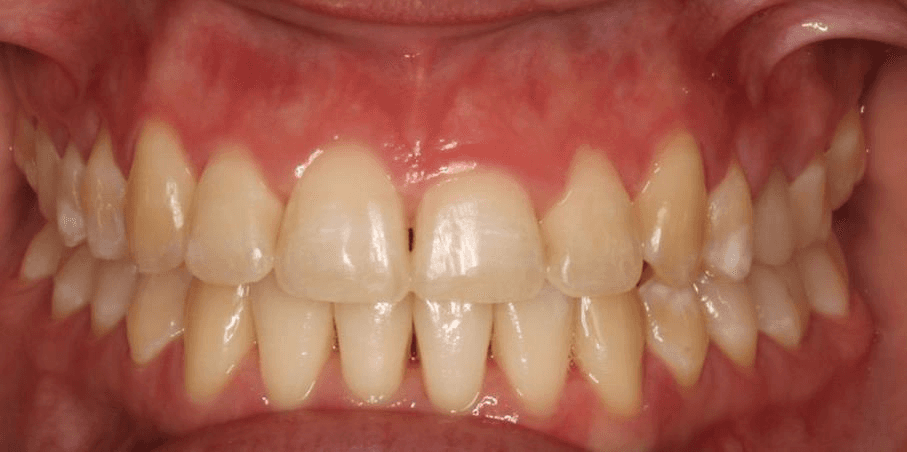

Diganosis: Moderate crowding in both arches, constricted arch forms with anterior and posterior single tooth crossbites, poor smile display

Initial treatment

INTRAORAL